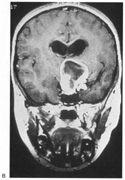

Most striate lesions are infarction, mainly from posterior cerebral artery occlusion (Fig. 14), with sudden onset visual loss and sometimes headache.53 In about half, the visual field defect is the only deficit,53 but in others damage to medial occipito-temporal regions causes amnesia, prosopagnosia, and color perception defects. A syndrome of agitated delirium and hemianopia occurs with lesions of the medial occipital lobe, parahippocampus, and hippocampus.54–56 Brainstem signs include impaired level of consciousness, III nerve palsy, dysarthria and hemiplegia.53 Causes of ischemia are most frequently cardiac emboli and vertebrobasilar occlusive disease; migraine is a rare cause of permanent defects.53 Hemorrhage, vascular malformations, primary and secondary malignancies are much less common.33

Fig. 14. Location and etiology of homonymous hemianopia in 140 patients. (From Fujino T, Kigazawa K, Yamada R: Homonymous hemianopia. A retrospective study of 140 cases. J Neuroophthalmol 6:17, 1986, Aeolus Press, with permission.)